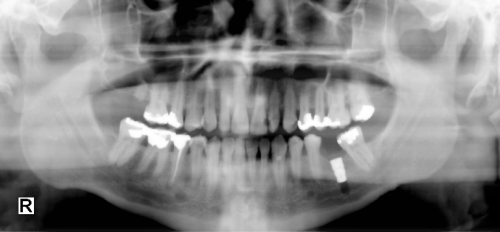

Tissue Equalize Function - Before